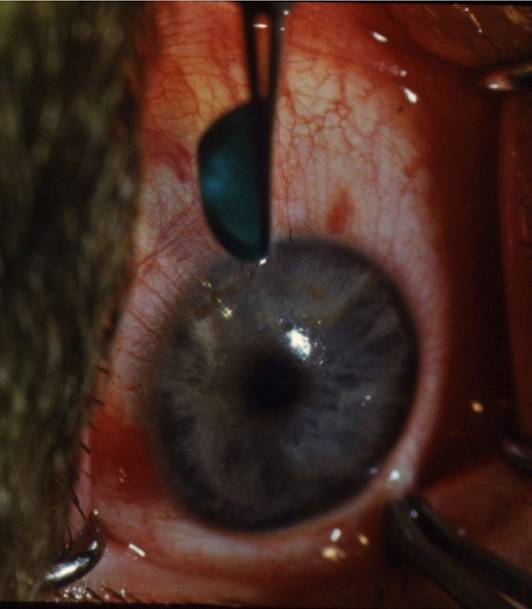

Рис.11.1.1. Схема операции секторальной рефракционной кератопластики

Рис. 11.2.4. Введение трансплантатов в секторальные тоннели

Рис. 11.2.5. Трансплантаты расположены в двух противоположных секторах

Рис.11.2.6. На фоне розового рефлекса - секторальный трансплантат

Рис. 11.2.7. Секторальная кератопластика по горизонтальному меридиану